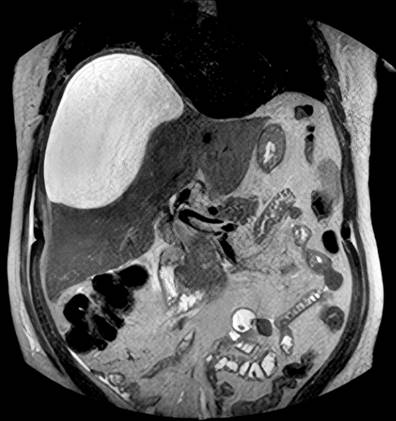

The patient underwent an abdominal ultrasound that described dilation of the bile duct with these measurements: the right route (5 mm), the left one (4.8 mm), and the confluence (5.3 mm). A low amount of gas was also described at the level of the intrahepatic bile ducts. He also underwent a magnetic resonance cholangiopancreatography where they found a focal alteration in the subcapsular region of hepatic segment VI with an image of 34 x 31 x 37 mm, of heterogeneous content and similar images of smaller size, 10 and 13 mm, in segment VIII, suspicious of abscesses. Hepatic subcapsular fluid was also documented in the right lobe (112 mL) (Figure 1) and intrahepatic bile duct dilation with images of microlithiasis in the right hepatic duct near the confluence and in the intrapancreatic segment of the common bile duct. After 48 hours, an abdominal MRI was performed, and an increased volume of the hepatic subcapsular collection was found (Figure 2), so the patient was inserted into a multipurpose catheter. In the procedure, 1600 mL of purulent biliary-looking fluid was drained. The patient continued for five days with biliary drainage of 350-500 mL daily through the multipurpose catheter and with signs of an inflammatory response, so he was taken to ERCP.

Figure 2 MRI of the abdomen. Increased volume of bilioma is observed. Image Archive of Hospital Universitario Hernando Moncaleano Perdomo in Neiva.